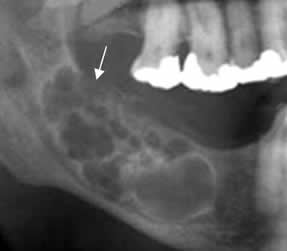

Fig 67. Queratoquiste odontogénico.

A: Rx AP y B: Rx oblicua. Imagen ovalada, de bordes bien definidos y escleróticos,

en el ramo de la mandíbula, por queratoquiste odontogénico.